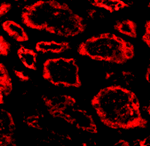

Immunofluorescence of Ski in human kidney tissue with Ski antibody at 20 ug/mL.